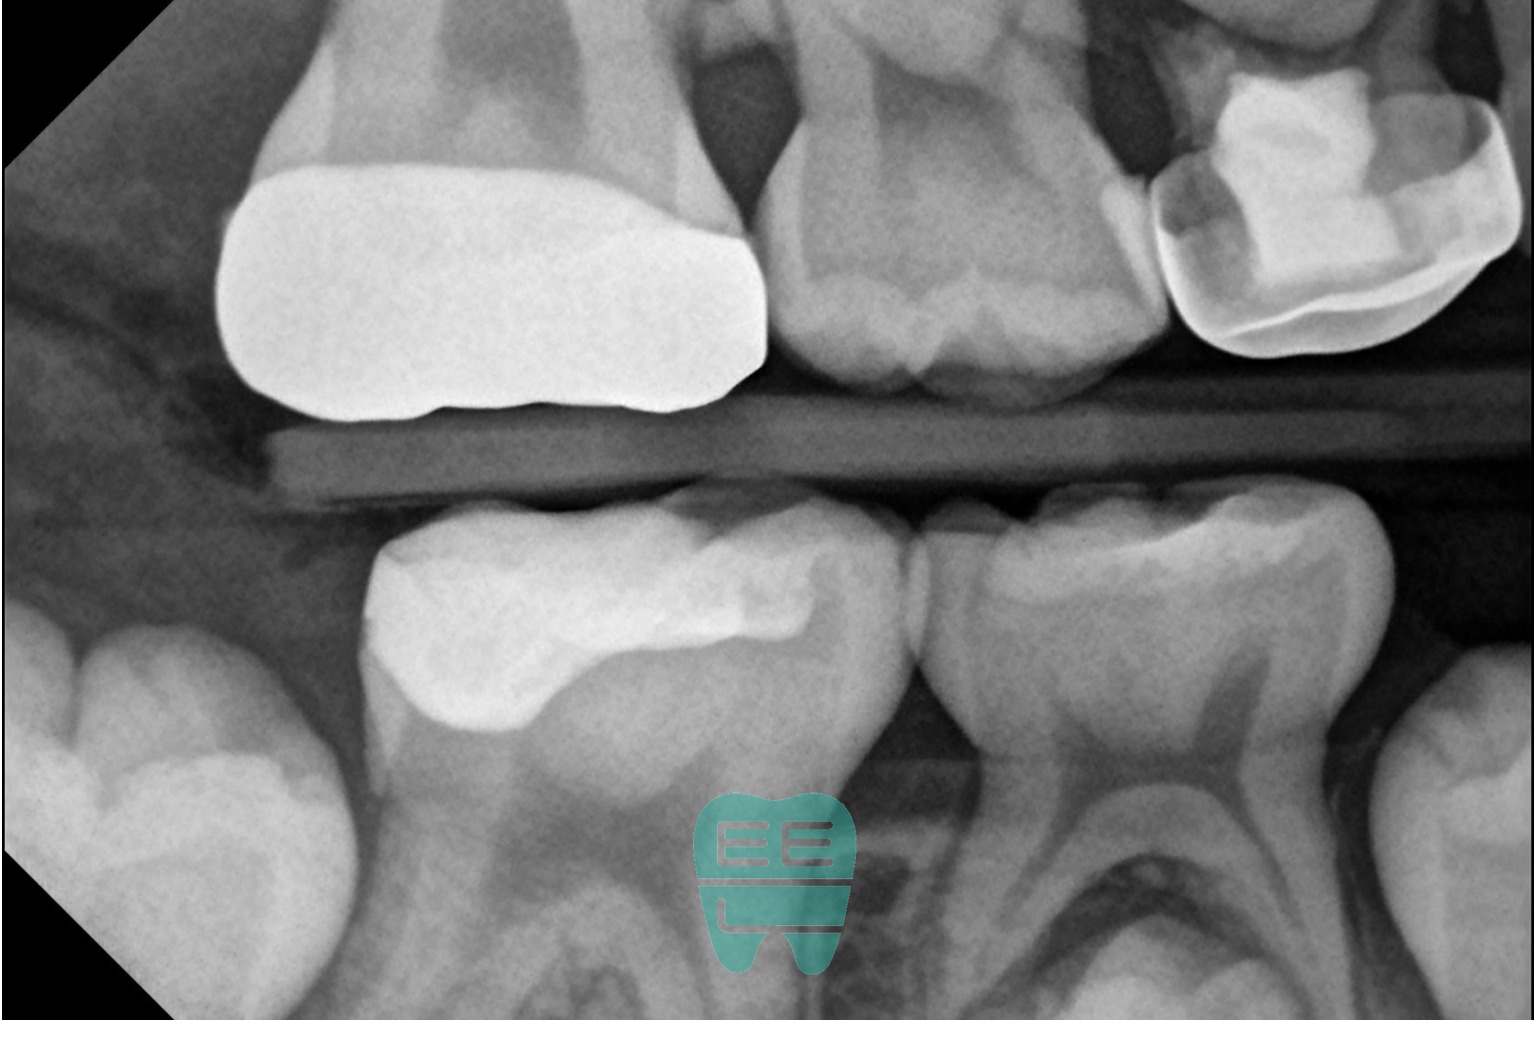

11. 치료 후 방사선 확인

치료 후 촬영한 교익방사선 사진에서도 적절한 형태가 관찰됩니다. 인접면 contour가 잘 형성되어 있고, 하방에 빈 공간 없이 레진이 잘 충전된 것을 확인할 수 있습니다.